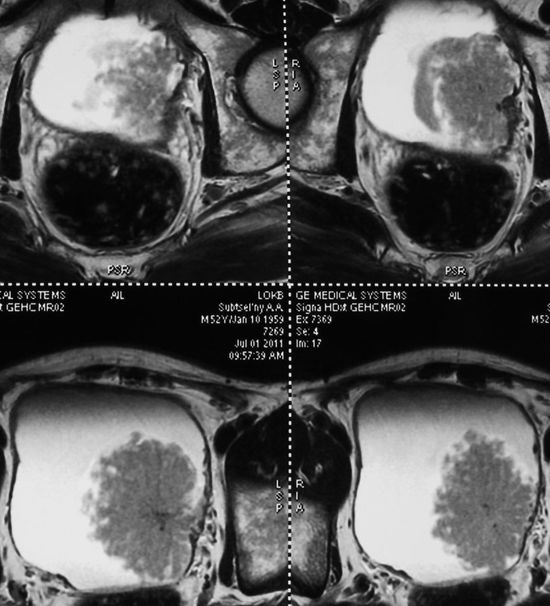

Гигантская опухоль правой почки. Экстримальная нефрэктомия.